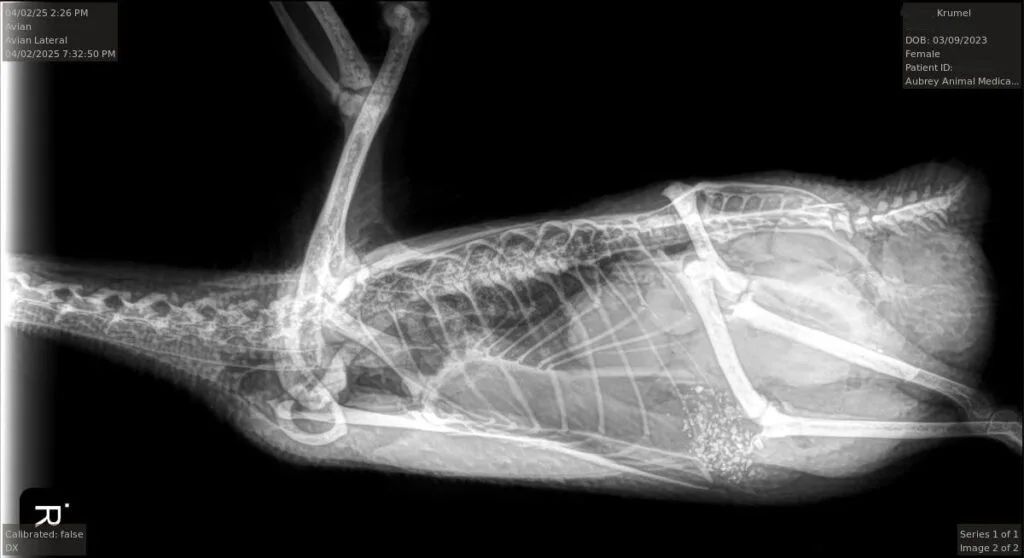

Bloodwork revealed elevated white blood cells (suggesting infection), abnormal pancreatic enzyme levels, and—most alarmingly—high levels of zinc, a possible sign of metal poisoning. An X-ray did not reveal any obvious metal object, but her symptoms were consistent with internal inflammation. Our vet suspected that she had either ingested something toxic or was suffering from a combination of reproductive distress and early systemic infection.

X-rays revealed a few soft-shelled eggs piling up inside her. Some of them had broken, leading to a serious infection. She began passing a foul-smelling mix of egg yolk and pus through her droppings. Our vet prescribed antibiotics again, and thankfully, Krümel has stabilized and is doing well for now.